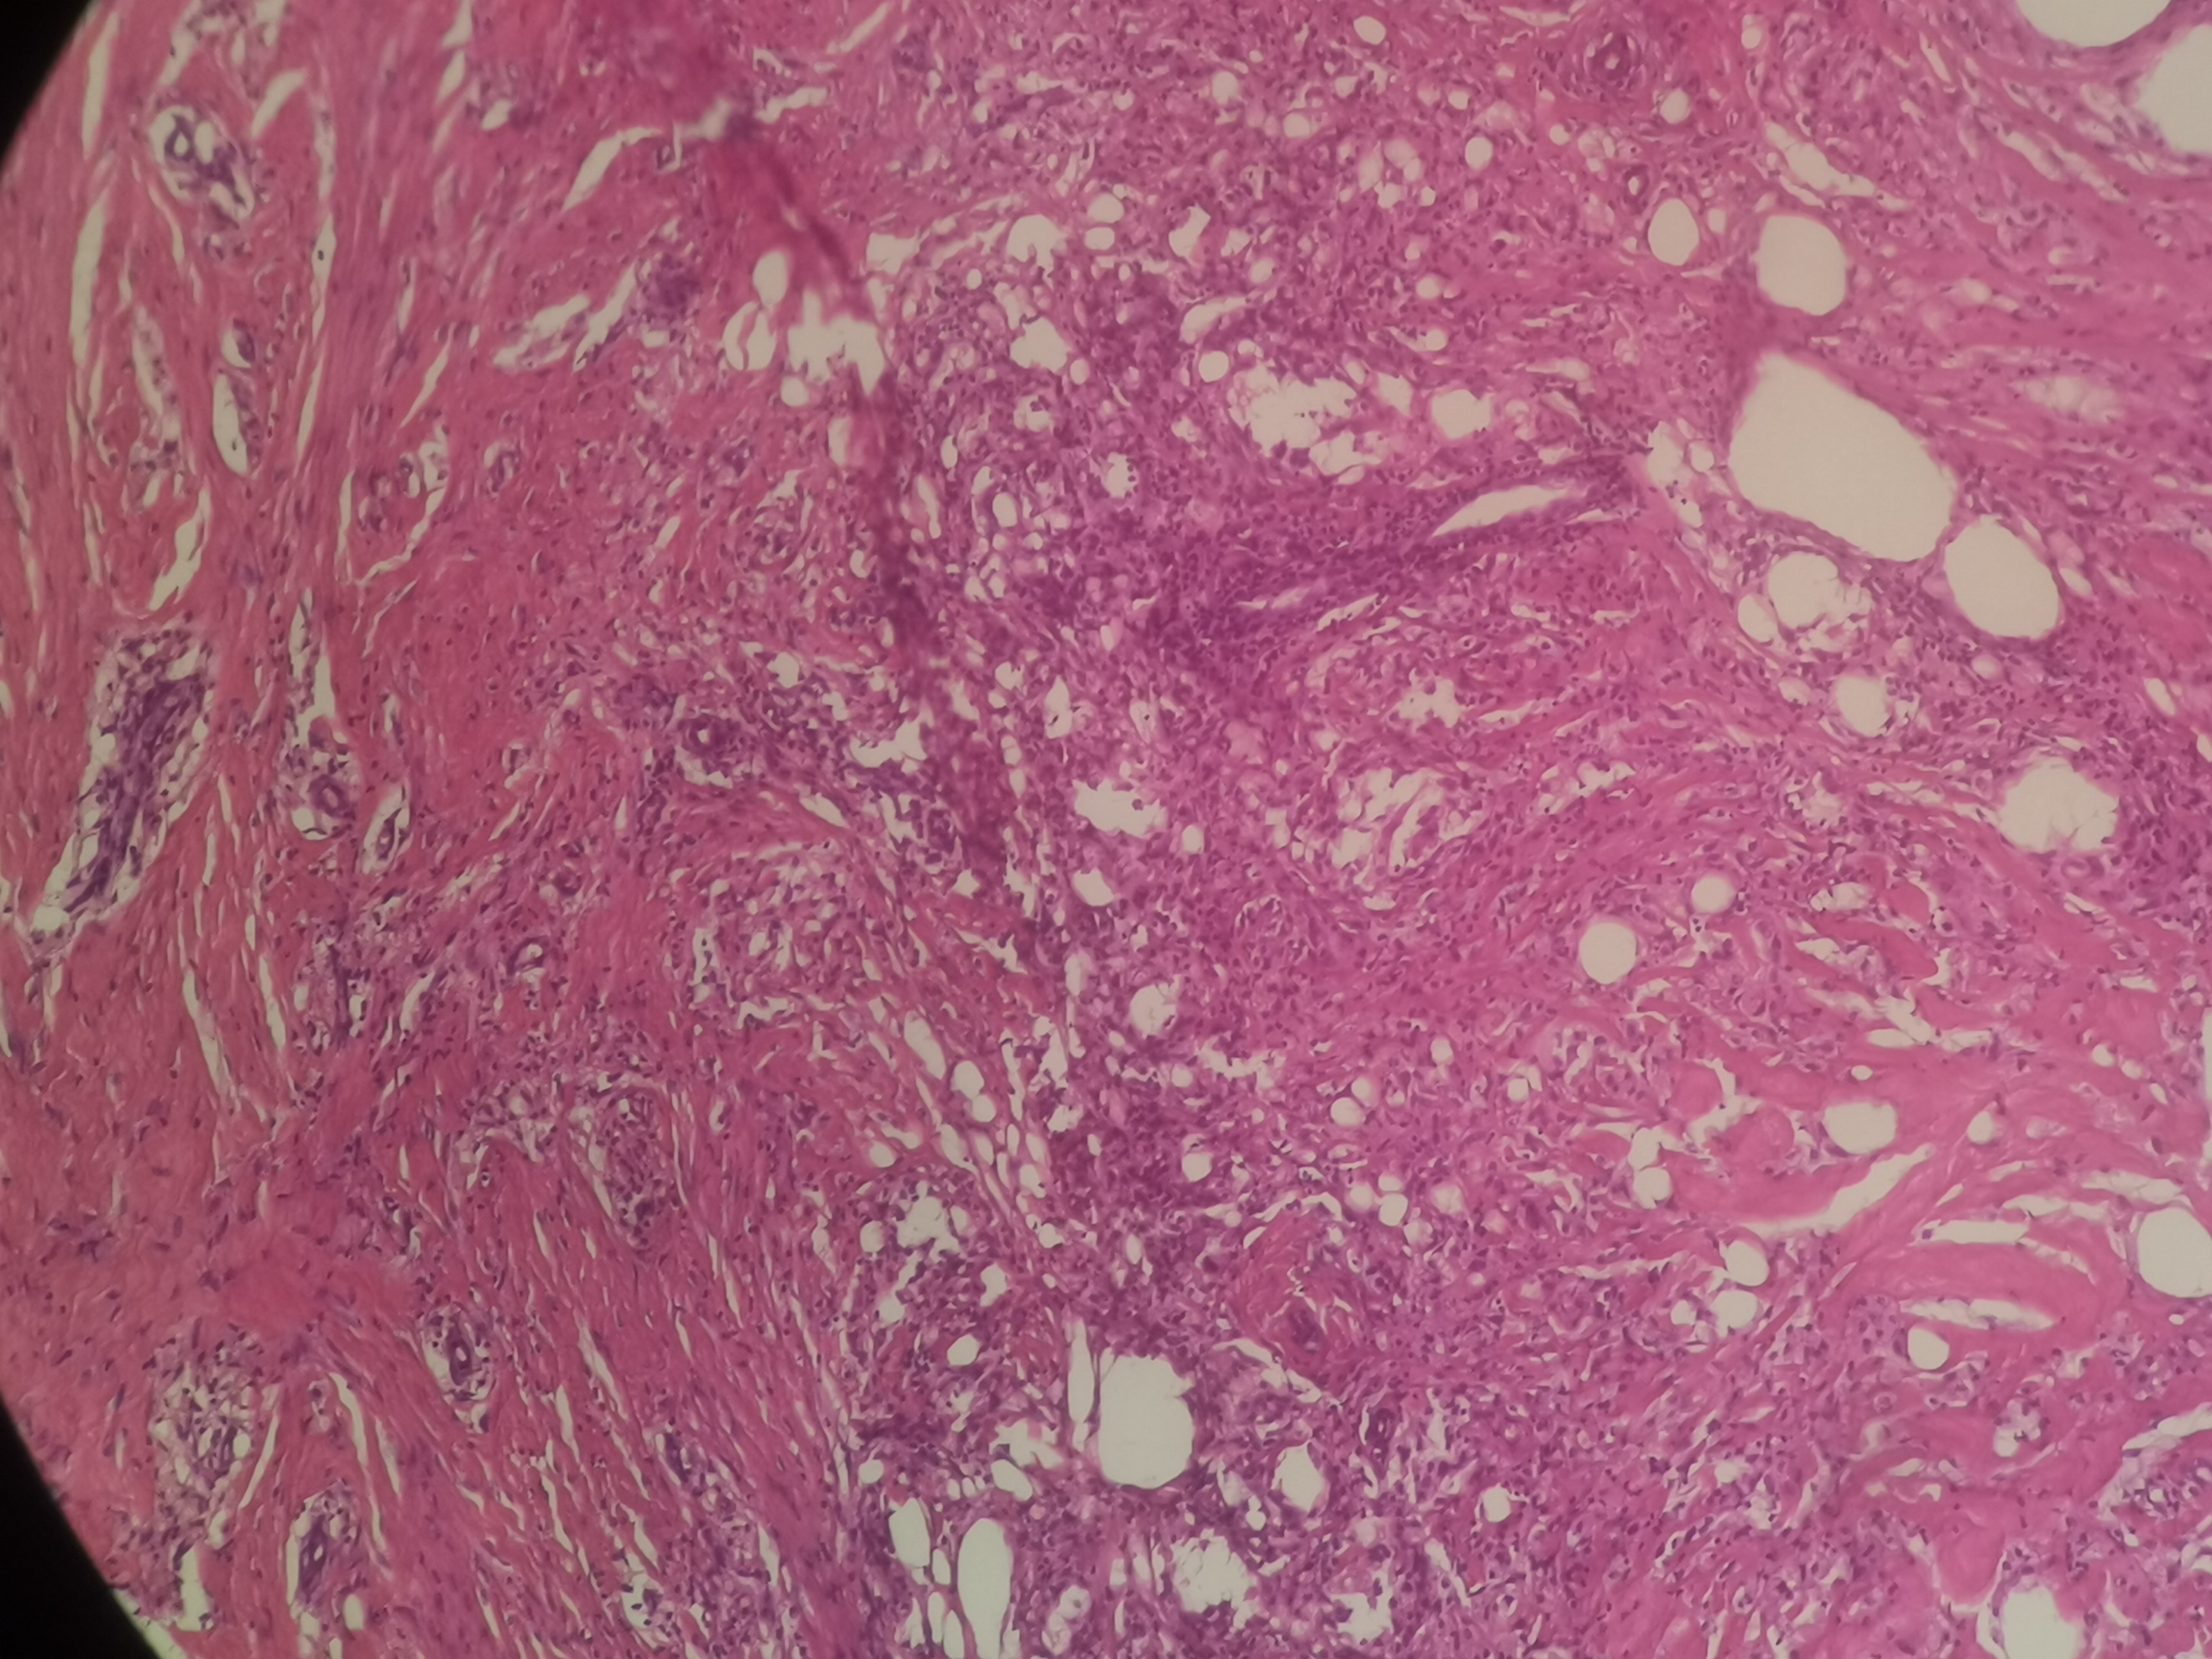

急!请老师帮忙看看,这个是脂肪坏死?

性别

女

年龄

31岁

临床诊断

左侧臀部肿物

一般病史

2个月前发现肿物,开始米粒大小,近几个月逐渐增大,触碰不适

标本名称

左侧臀部肿物切除术

大体所见

脂肪样组织4.2x1.9x0.6厘米,未见明显包膜,切开见囊腔,约2.4x1.3厘米,并见黄脓性粘稠物流出。

超声:皮下脂肪低回声结节,1.1x0.8厘米,0.9x0.6厘米,边界清,形态尚规则,内部呈无回声,诊断左侧臀部低回声包块。

脂肪坏死伴肉芽肿性炎